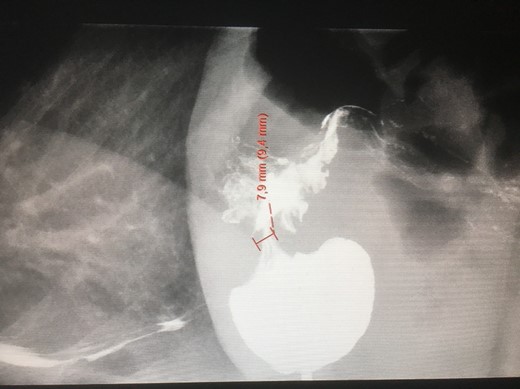

A 60-year-old female, who had undergone gastric banding in 1985, was referred in February 2018 to our institution due to malnutrition and weight loss. Her weight and height were 66 kg and 168 cm, respectively. She had developed increasing malnutrition problems due to a stenosis in the stomach (due to gastric banding) and could not eat regular food. Her food intake was a liquid diet in terms of various soups and nutrition drinks. A blood test relieved normal values of hematology, electrolytes, and kidney and liver functions. A gastroscopy documented a 6 cm long upper part of the ventricle and a two cm long stenosis. An X-ray of esophagus, stomach and duodenum (Fig. 1) revealed a very slow passage through the stenosis. After 15 min the barium agent had passed through the stenosis. The diameter of the stenosis was measured by the radiologist to be 8 mm. There was still barium contrast left in the upper part after 12 h.

An X-ray of the stomach with gastric banding and a stenosis. Barium has been administered.